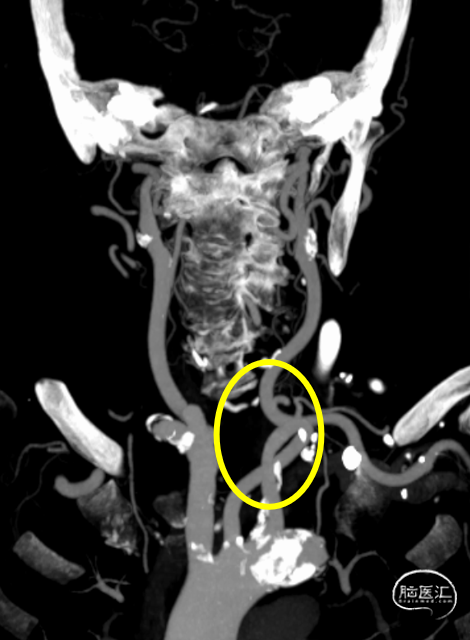

动脉早期冠状位残端

动脉早期水平位残端

颈总动脉迂曲

颈内动脉